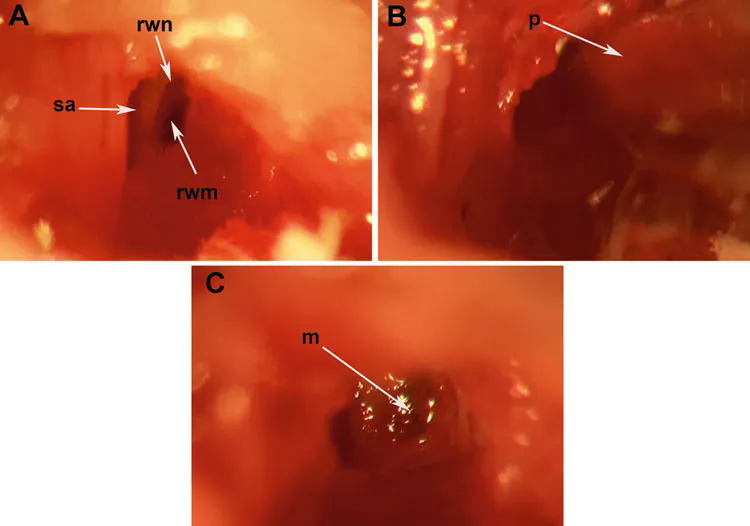

1、圓窗膜(RWM)注射

6) 用(yong)25G針在鼓室大皰(pao)上(shang)穿(chuan)孔,然后充分擴大以可(ke)見(jian)鐙骨動(dong)脈(SA)������和圓窗膜(RWM);

7) 用硼(peng)��������硅(gui)酸(suan)鹽毛細管移液(ye)(ye)管在(zai)RWM中心(xin)輕輕穿刺,觀察液(ye)(ye)體(ti)通過RWM的流(liu)出情況(耳蝸�����流(liu)出的液(ye)(ye)體(ti)用無菌(jun)濾紙干燥);

8) 在(zai)射流穩定后(5-10 min),將0.6~2μL�������的AAV載體通過RWM注射到耳蝸(gua)鼓階�����;

9) 拔(ba)出移液管后,用一(yi)小塊肌肉(rou)組織(zhi)迅速密封RW����龕,并在肌肉��������(rou)上滴一(yi)小滴組織(zhi)膠固定,以避免耳蝸周圍淋巴液通過RWM滲漏(lou);

圖(tu)5. 圓窗膜(mo)(RWM)注(zhu)射

(Akil O, et al.Methods Mol Biol. 2019)